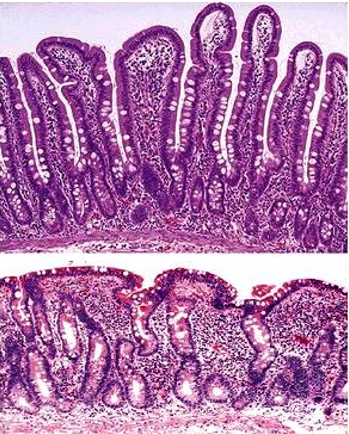

What do you expect to see on biopsy of someone with Celiac Disease?

**Shown here is normal tissue on the top and celiac disease tissue below

Scalloping shown here is likely due to Celiac Sprue